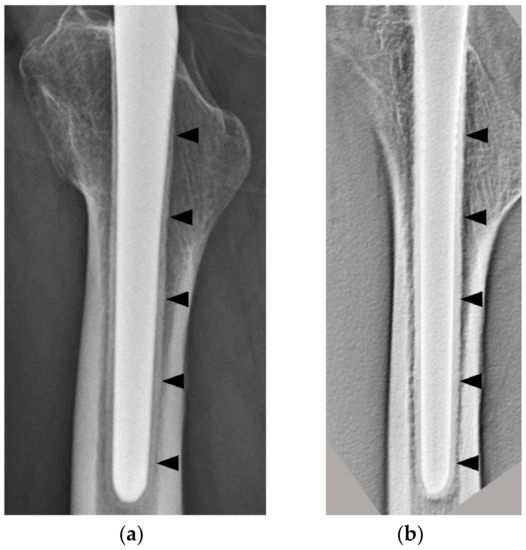

In the AP view, the thicknesses of the osteogenic layer were 0.54 ± 0.19 and 0.91 ± 0.31 mm in the 1 y group and 3 y group (p < 0.001), respectively, and there was a significant difference. In the lateral view, the thicknesses of the osteogenic layer were 0.69 ± 0.20 and 1.16 ± 0.27 mm in the 1 y group and 3 y group (p < 0.001), respectively, and this was also significantly different (Figure 5). No RLs with osteopetrosis in either group were noted.

Figure 5.

In both AP and lateral views, the 3 y group had a significantly thicker bone formation than the 1 y group (p < 0.001). AP, anterior–posterior.